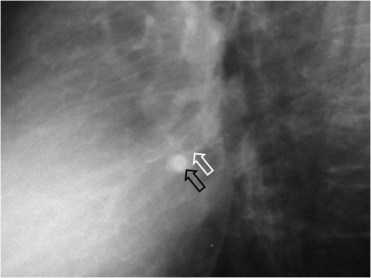

SIGNO DEL MONÓCULO

Signo que permite diferenciar una arteria pulmonar de un nódulo pulmonar. Una arteria vista de frente, aparece como una densidad redondeada similar a un nódulo (flecha negra); sin embargo puede diferenciarse al ver el bronquio que la acompaña como anillo denso que rodea un círculo radiotransparente (flecha blanca).